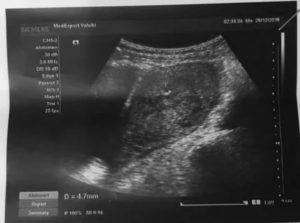

Плодное яйцо — это защитные оболочки, окружающие зародыш. Они прикрепляются к стенке матки, образуя с ней сосудистую связь. Через сосуды растущий зародыш получает питание из материнской крови. Плодное яйцо на УЗИ выглядит, как округлое образование темно-серого цвета.

Оно становится видным, когда достигает размера 5 мм. Это соответствует 4 неделям беременности. Эмбрион внутри яйца пока не виден. Его можно рассмотреть после 35-го дня, выглядит он как темная полоска. Части его тела можно увидеть на 12 неделе беременности — в этот срок обычно и проводят первое обследование.

С помощью этого способа беременность точно подтверждается в сроке 28 дней. Второй метод — трансабдоминальный. Осмотр проводят через переднюю брюшную стенку.